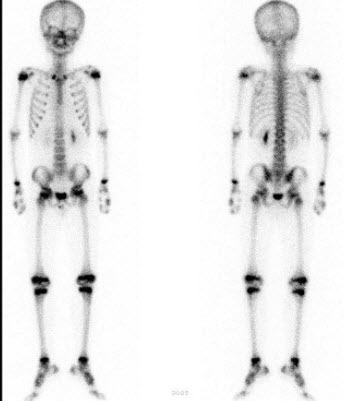

男性38岁,左图为甲状旁腺瘤术前骨显像,右图为3个月后的术后骨显像。正确的描述是()

A.左图箭头表示软组织的永久钙化

B.左图箭头表示软组织的迁徙性钙化

C.两幅图均提示代谢性骨病,右图表明术后恢复正常的骨显像

D.右图提示肾性骨营养不良

E.以上都不是